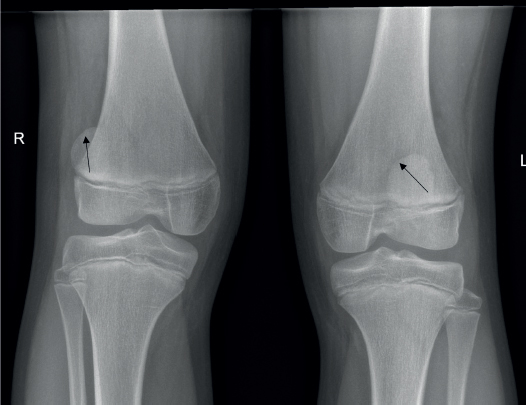

NPS is a rare genetic autosomal dominant disorder, characterised by hypoplastic nails and patellae, and the presence of a bilateral extra piece of iliac bones on both sides ‘iliac horns’ in pelvic X-ray [14]. The image in our case (Figure 1) clearly shows ‘posterior horns’ of both iliac bones where the posterior aspects of both iliac bones are not even or straight, they are curved and appear like ‘horns’ (Figure 1, arrows), the presence of which is pathognomonic of this rare disorder [14]. The child had other features of the disease such as scoliosis and hypoplastic thumb nails. Both patellae were mildly hypoplastic and the right patella was displaced laterally (genu varum) (Figure 2, arrows).

Figure 2. X-ray of both knees. Both patellae were mildly hypoplastic and the right patella was displaced laterally (genu varum).